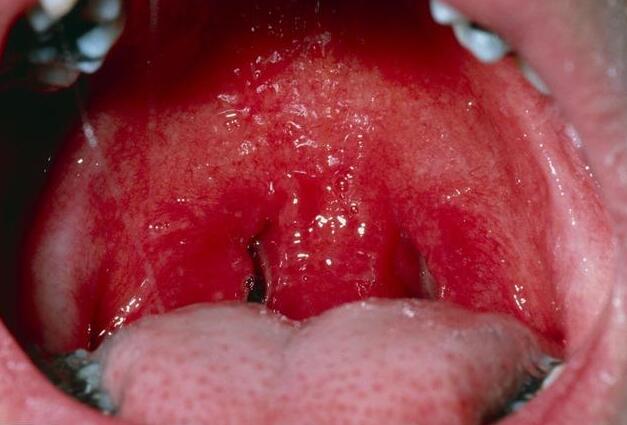

2、急性的充血、水肿,主要是鲜红色的或者是充血非常明显的。慢性的充血,主要是暗红色的,充血、水肿不明显。

3、临床表现,急性主要是疼痛,甚至出现发热、咽喉部的各种不适。慢性的主要是咽喉部的各种不适,感觉甚至没有什么特殊的,仅仅是因为咽喉部黏膜的稍微充血。